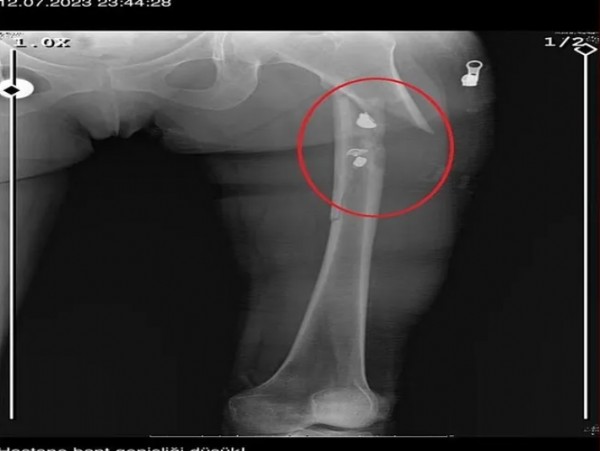

İlyas Sarıkaya, sevgilisi Fatma O.'yu da 8 kurşunla vurup, yaraladı. Arkadaşı Özaslan'ın cesedini önce çarşafa sonra da streç filme sarıp bantlayan Sarıkaya, eczaneden aldığı sargı bezi ve ilaçlarla pansumanını yaptığı sevgilisine yaralı haldeyken 21 gün boyunca cinsel saldırıda bulundu.

Fatma O., annesine yazdığı mesajda, 'Odada ceset var. Telefon dinleniyor. Bana 8 el ateş etti. Yaralıyım. Polisi görürse önce beni öldürecek. Onu parayla kandırıp, evden çıkartın. Sonra da beni alın' dedi. Fatma O.'nun annesi, bu mesaj sonrası polise gidip şikayette bulundu. Polis, Fatma O.'nun annesi aracılığıyla Sarıkaya ile iletişime geçti. Fatma O.'nun annesi, telefonla aradığı Sarıkaya'yı, kızına para götürmesi için evine çağırdı. Ekipler, parayı almaya gelen Sarıkaya'yı kendilerine silah çekmesine rağmen yakaladı. Eve giden ekipler, ağır yaralı haldeki Fatma O. ve kokmaya başlayan cesetle karşılaştı. Emniyetteki işlemlerin ardından Sarıkaya tutuklanıp, hakkında dava açıldı.